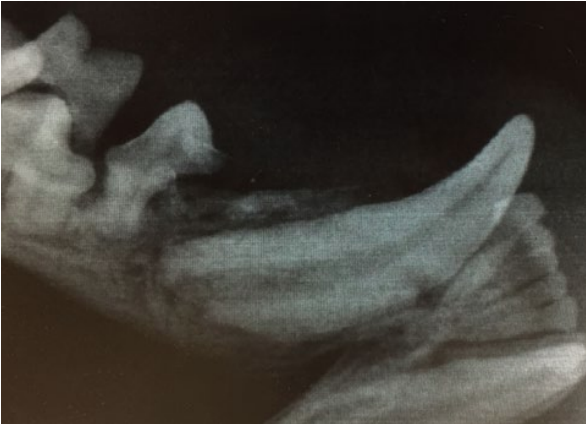

- Метаболические нарушения (такие патологии, как гипотиреоз и вторичный гиперпаратиреоз). На фото 4 представлен пациент – кошка (возраст – 1 год и 1 месяц), у которой сохранены временные 707, 807 зубы. Рентгенографическое исследование того же пациента (фото 5–7) выявило резорбцию зубов, незавершенные апексы, периодонтит, наличие ретенированных предшественников 307 и 407 зубов.